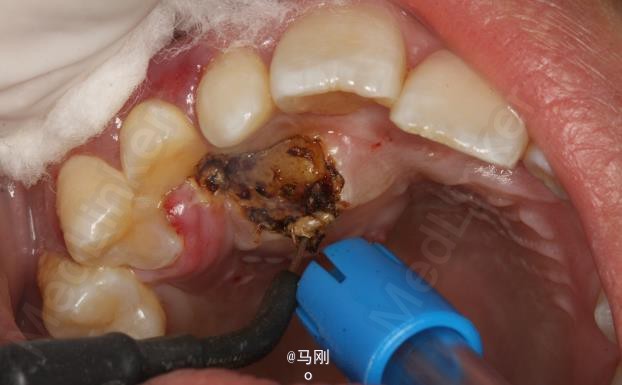

诊断 处理

处理:建议拔除右侧乳尖牙,并外科开窗牵引导萌13。患者同意治疗方案。签知情同意书。